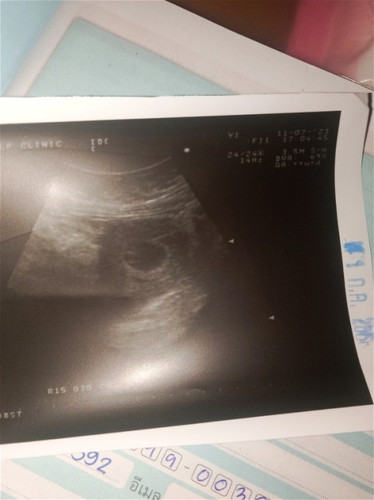

แอบกังวนคะแม่ท้องตอนนี้9สัปดาห์แล้วแต่ทำไมยังไม่เจออะไรเลยคะเจอแต่ถุงคะแม่ๆบ้านไหนเจอน้องเร็วกว่านี้ไหมคะวันที่25คุณหมอนัดตรวจอีกคะคุณหมอบอกน่าจะเจอน้องแต่แม่ก็อดกังวลไม่ได้คะกลัวไม่เจอน้องแต่ขอไห้ความโชคดีเกิดกับเราด้วยเถอะแม่ๆเจอน้องกันกี่วีคคะนี่เราท้อง2คะคนแรกไปหาหมอก็เจอน้องเลย#ขอบคุณสำหรับคำตอบค่ะ

บ้านนี้ไปฝากครรภ์ครั้งแรก7W2D ซาวด์หน้าท้องไม่เจออะไรเลยค่ะ เลยซาวด์ผ่านทางช่องคลอด เจอตัวน้องค่ะ และได้ยินเสียงหัวใจเต้นแล้วค่ะ พอ8W ซาวด์หน้าท้องดูอีกก็ไม่เจอค่ะ หมอนัดอีกทีวันที่28นี้ค่ะ แม่ก็ยัง งงๆ ทำไมซาวด์ทางหน้าท้องไม่เจอค่ะ ของคุณแม่ได้ลองซาวด์ผ่านทางช่องคลอดรึยังคะ

เป็นเหมือนกันเลยค่ะ ตอนนี้เราท้องได้ประมาณ6-7สัปดาห์แล้วค่ะไปซาวเจอเเต่ถุงเหมือนกันหมอนัดซาวอีกเดือนน่า แอบกังวลยุเหมือนกันค่ะ สู้ๆไปด้วยกันนะคะแม่🥹✌🏻

ของเราท้องแรกเราไปฝากครรภ์ตอน12วีค เจอน้องเลย พอตอนนี้ท้อง2เราไปตั้งแต่6วีค แต่ไม่เจอน้องค่ะ หมอเลยนัดมาซาวด์อีกครั้งตอน9วีค ท้อง2เราเจอน้องตอน9+3ค่ะ

ปกติถ้า7wบางคนเจอ บางคนไม่เจอ แต่เท่าที่เจ้าของกระทู้บอกคือ9w จะต้องเจอตัวน้องแล้วนะคะ ของเรา7wไปซาวไม่เจอ เจอแต่ถุง หมอนัดอีกตอน9w ไปซาวเจอน้องค่ะ

เราก็แอบกังวลเลยค่ะ เพราะตอนตรวจ 6 w1 d เจอแต่ถุงการตั้งครรภ์ หมอนัดอีกทีตอน9w1d ภาวนาจิให้เจอน้องที ลูกคนแรก รอมา 8 ปีเต็ม

เหมือนกันค่ะ 7-8 w ไปซาวด์เจอถึงตั้งครรภ์แต่ไม่เจอน้องหมอเลยให้โอกาสนัดซาวด์อีกวันที่ 25 นี้ค่ะ ลุ้นๆเหมือนกันค่ะ

บ้านนี้ไปซาวด์10วีคเจอแต่ถุง หมอนัดอีกที่1 ส.ค. ลุ้นเหมือนกันคะ แต่ไม่มีภาวะปวดท้องรึเลือดออกเลยนะคะ